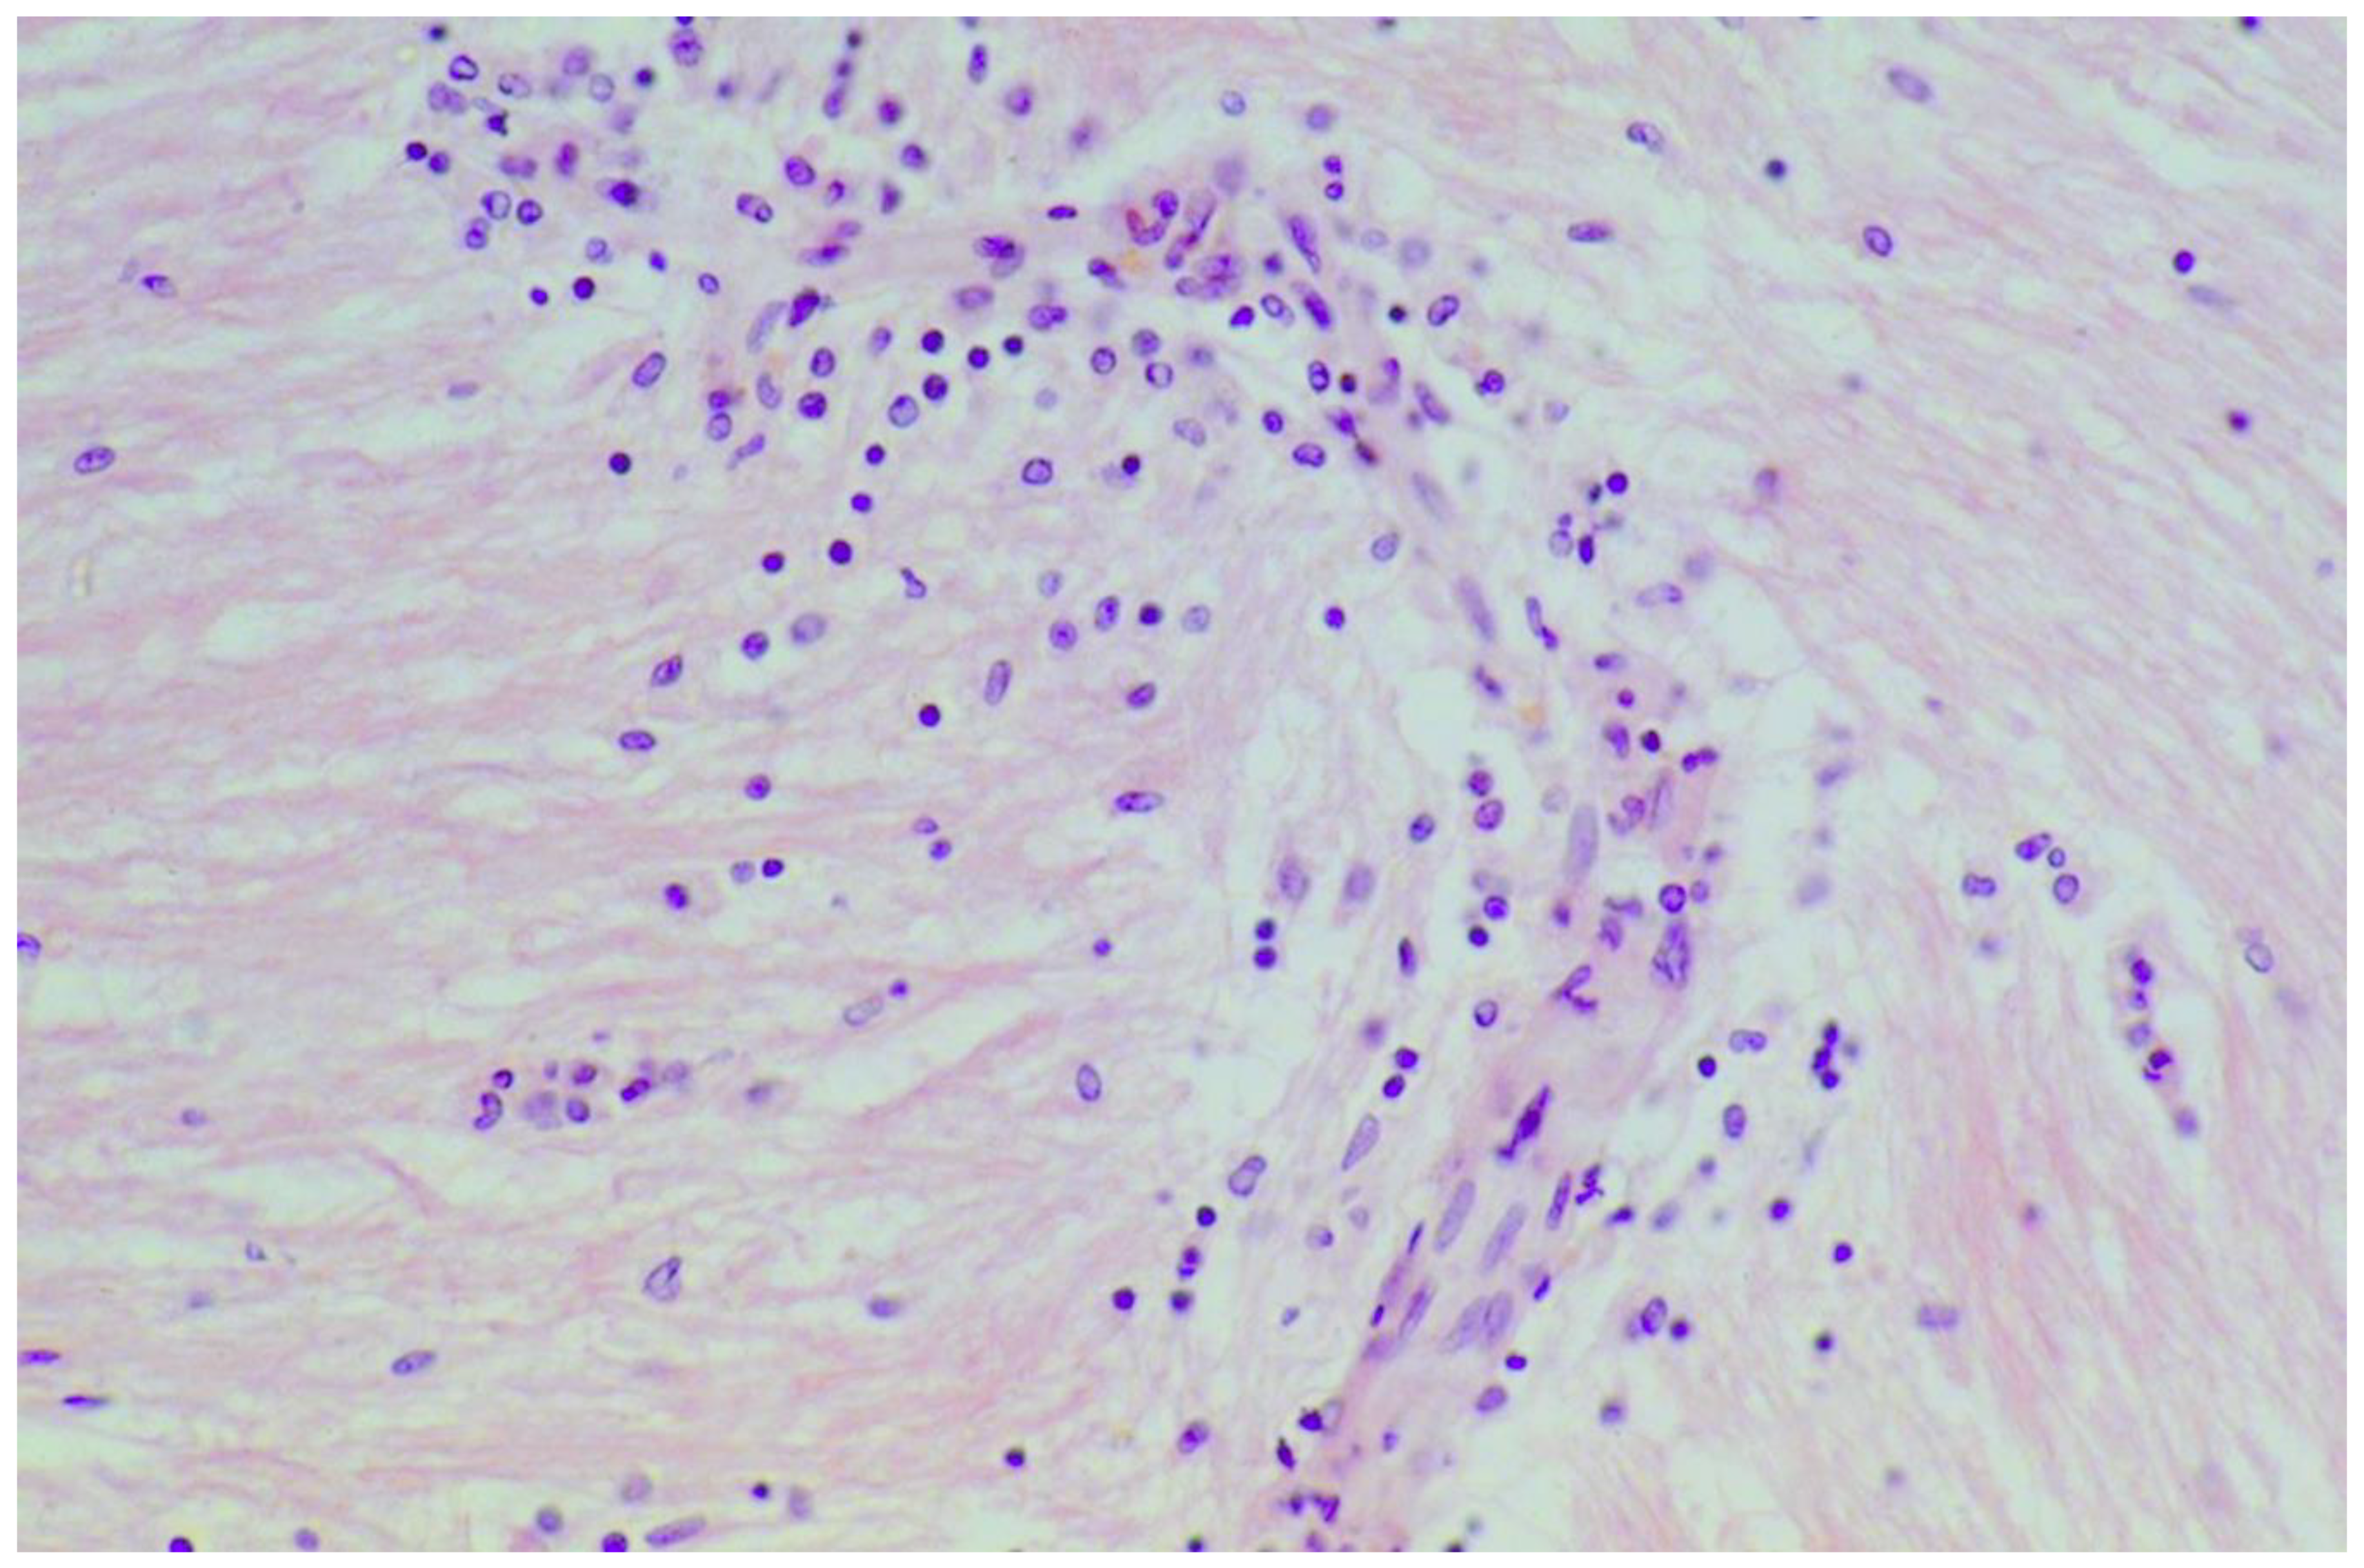

| Hadjivassiliou 2007, UK | 13 | Muscle | Internal nuclei; Basophilic rimmed vacuoles; fiber splitting; Endomysial chronic inflammatory cell infiltrate (CD3+ cells), Fibrosis |

| Danielsson 2017, Sweden | 13 | Muscle | Inflammatory infiltrates & muscle fiber degeneration |

| Hadjivassiliou 1997, UK | 2 | Muscle | Inflammatory myopathy & Basophilic rimmed vacuoles |

| Alawneh 2008, Jordan | 1 | Muscle | Muscle necrosis; Neutrophilic infiltration; Secondary leukocytoclastic vasculitis |